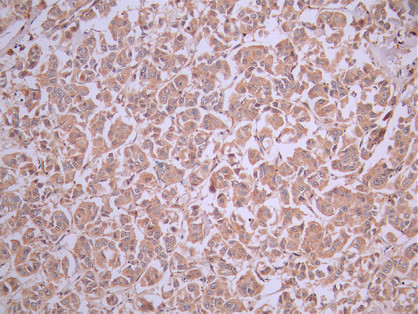

IHC image of CSB-RA118372A0HU diluted at 1:100 and staining in paraffin-embedded human breast cancer performed on a Leica BondTM system. After dewaxing and hydration, antigen retrieval was mediated by high pressure in a citrate buffer (pH 6.0). Section was blocked with 10% normal goat serum 30min at RT. Then primary antibody (1% BSA) was incubated at 4°C overnight. The primary is detected by a Goat anti-rabbit polymer IgG labeled by HRP and visualized using 0.05% DAB.